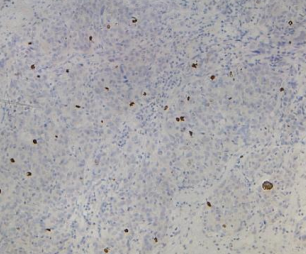

扁桃體用PHH3(GT2193)染色,腫瘤細(xì)胞胞核著色,DAB染色

腦膠質(zhì)細(xì)胞瘤用 NeuN(GT2194)染色,腫瘤細(xì)胞胞核著色,DAB顯色